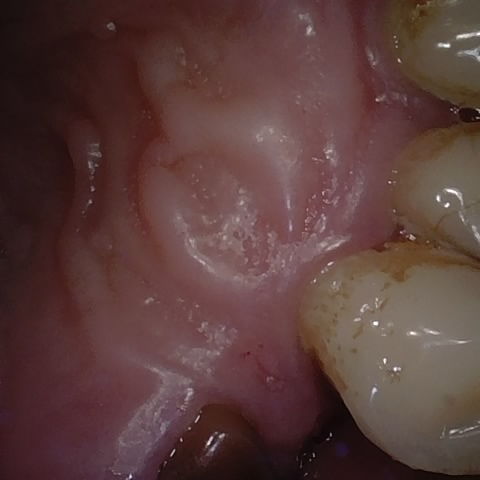

Annotated as "Good"